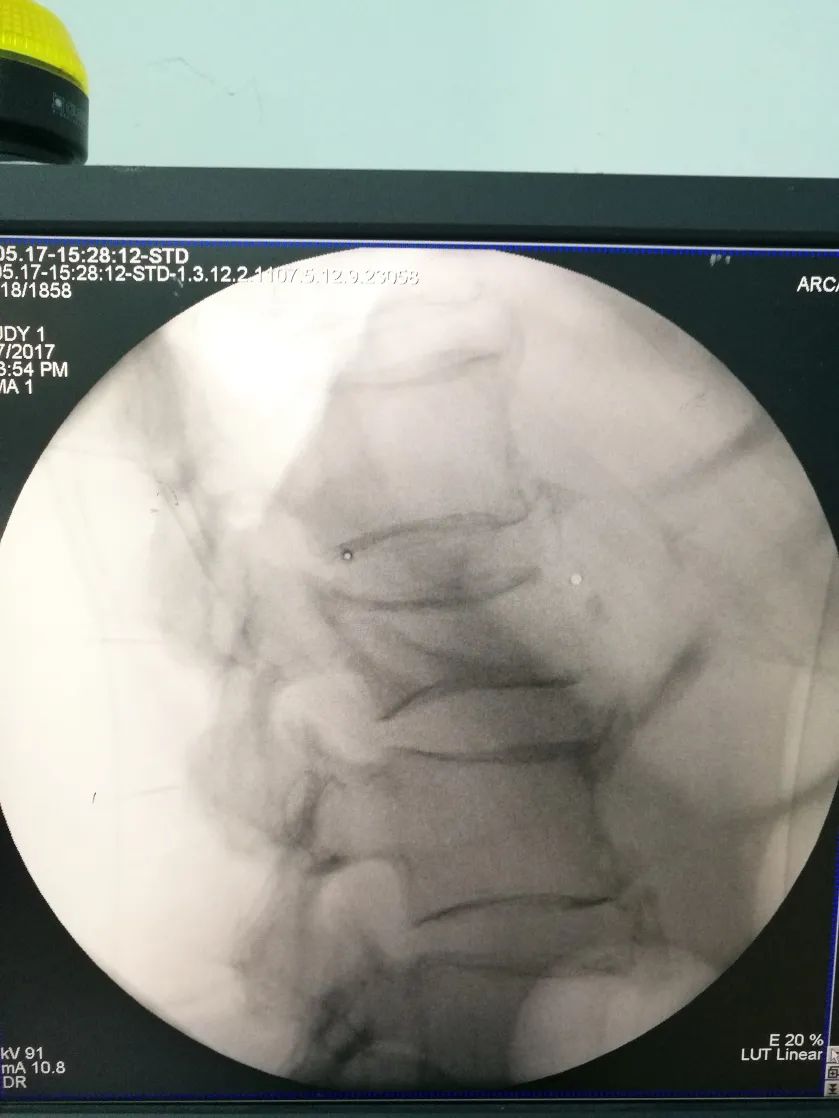

俯卧过伸位片

术中透视